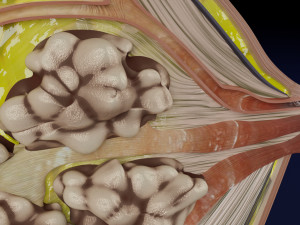

This is a 1:1 scaled model of right breast cut opened in sagittal plane to reveal its internal antomy and histology (schematic). The deeper parts and fascial layers are also depicted to give a very detailed approach to the model. The full layers starting from skin, nipple areola, till intercodtal muscles and ribs are also depicted.